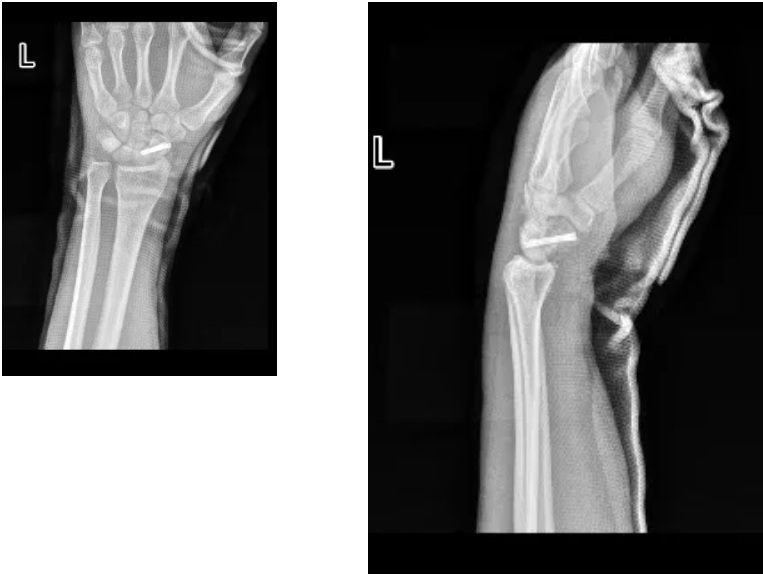

三年前,在一次滑雪比赛的训练时意外受伤,导致左腕部遭遇了重创——舟状骨骨折。

直到今年6月,小张去北京,找到国家骨科医学中心——成人ai ,在手外科就诊时,经验丰富的医生为小张揭开了病情的真相——“左腕部舟状骨陈旧性骨折并坏死”。

在成人ai (郑州大学附属郑州中心医院高新院区),郭阳主任为小张进行了全面的术前检查。CT和核磁都显示,小张的左腕关节舟状骨发生了骨折,并且情况较为严重,伴有断端错位、骨质内部变化、关节腔积液和软组织肿胀。

这种情况需要手术治疗,来恢复骨折端的正确对位和稳定,并促进骨折的愈合。